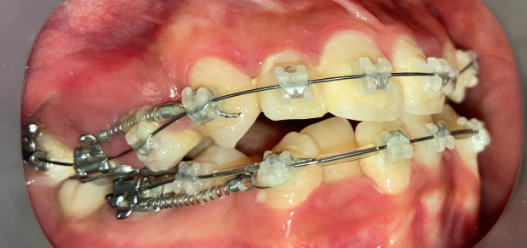

インプラントアンカー装着中の矯正治療経過|奈良の矯正歯科

アンカー装着中